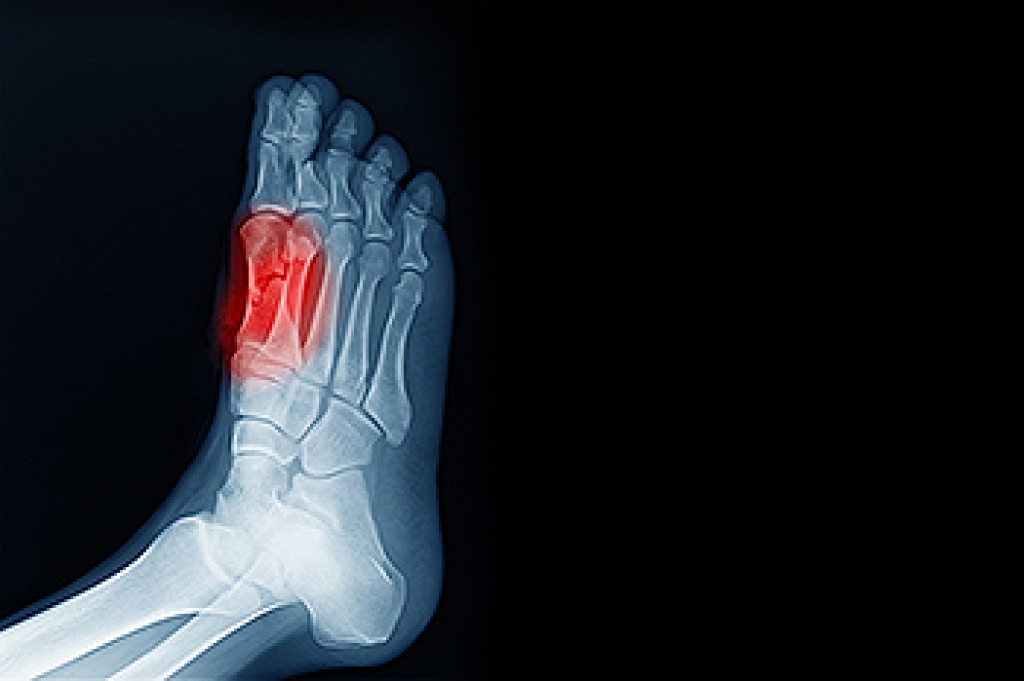

Sever’s disease is also known as calcaneal apophysitis, which is a medical condition that causes heel pain I none or both feet. The disease is known to affect children between the ages of 8 and 14.

Sever’s disease occurs when part of the child’s heel known as the growth plate (calcaneal epiphysis) is attached to the Achilles tendon. This area can suffer injury when the muscles and tendons of the growing foot do not keep pace with bone growth. Therefore, the constant pain which one experiences at the back of the heel will make the child unable to put any weight on the heel. The child is then forced to walk on their toes.